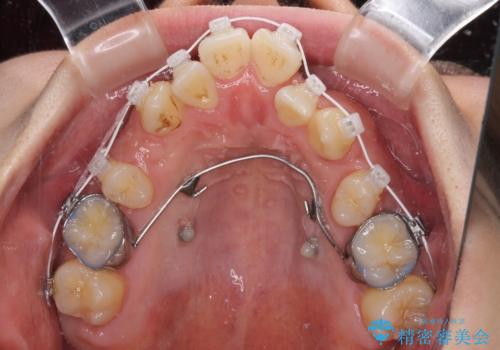

叢生が著しいため、上下左右の小臼歯4本を抜去し、目立たないワイヤー装置にて矯正治療を行うこととしました。

下顎の歯列全体が右側にずれているため、右下のみ第二小臼歯を抜歯し、上顎は補助装置を使用して、極力上下の正中を合う位置にて咬み合わせを改善するようにしました。